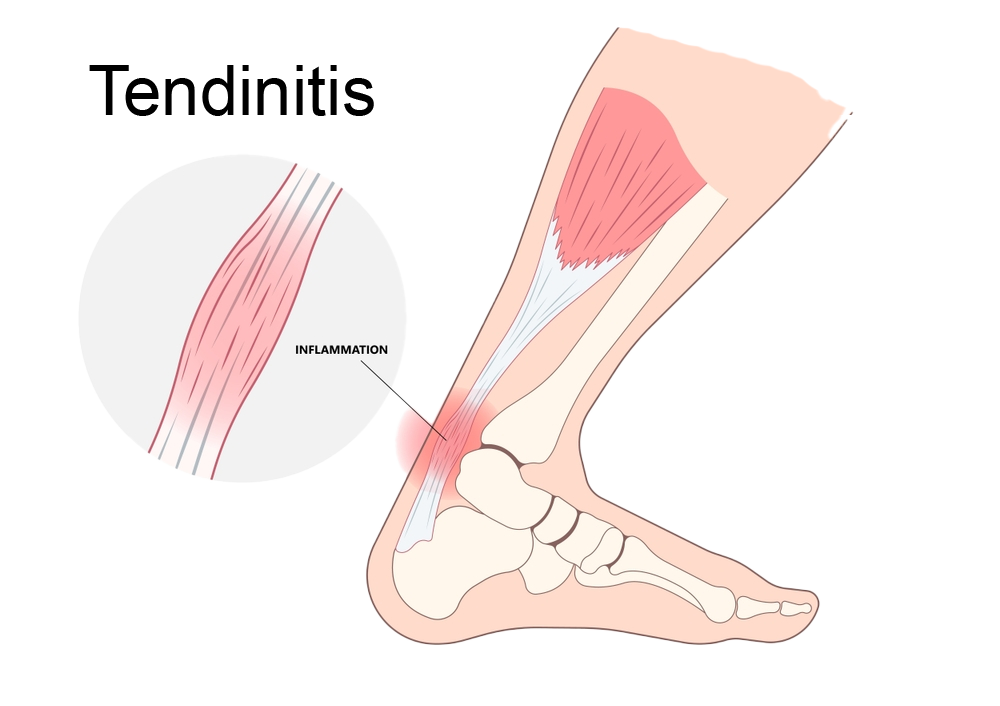

What-is-Tendinitis

Tendinitis

Inflammation of the tendons, particularly in the rotator cuff, leading to pain and restricted movement.